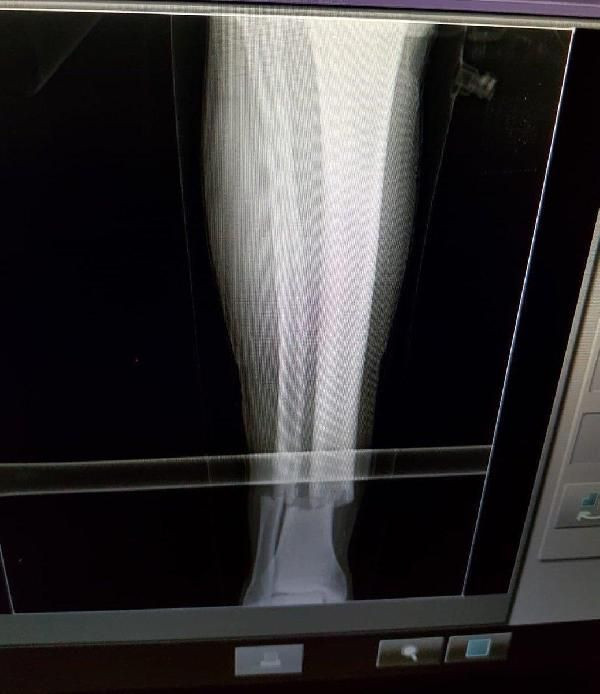

Öte yandan Emre Akbaba'nın röntgen filmi ortaya çıktı.

Sarı kırmızılı kulüpten yapılan açıklamada, "Oyuncumuz Emre Akbaba'nın sağ cruris tibia ve fibula (kaval ve baldır) kemiklerinde kırık mevcuttur. İlk müdahalesi yapılan oyuncumuz bugün sponsor hastanemiz Medical Park'ta ameliyata alınacaktır" denildi.

Sedye ile saha kenarına alınan ve ambulans ile hastaneye kaldırılan genç oyuncunun, kaval kemiğinde kırık olduğu öğrenildi.